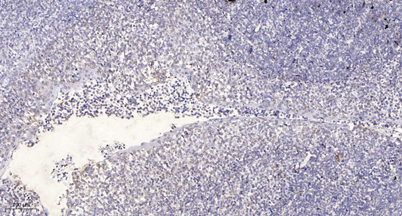

Recomended Dilution WB 1:500-2000 Immunohistochemistry: 1/100 - 1/300. ELISA: 1/20000. Not yet tested in other applications.